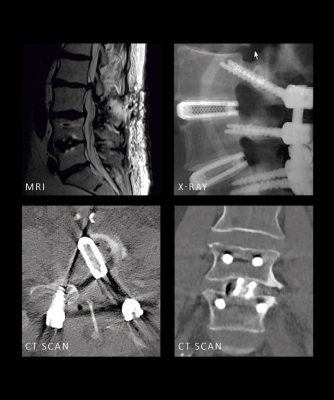

With a high coefficient of friction for enhanced primary stability and fusion clinically proven at 12 months, this solution delivers performance supported by peer-reviewed studies — from primary stability to long-term success.

Ti-LIFE Technology promotes rapid and effective bone integration, with significant osseous in-growth observed as early as four weeks post-operatively. Acting as a scaffold for osteogenic (bone-building) cells, the porous titanium structure facilitates bone growth not only through the implant but also around it, supporting robust and reliable fusion.